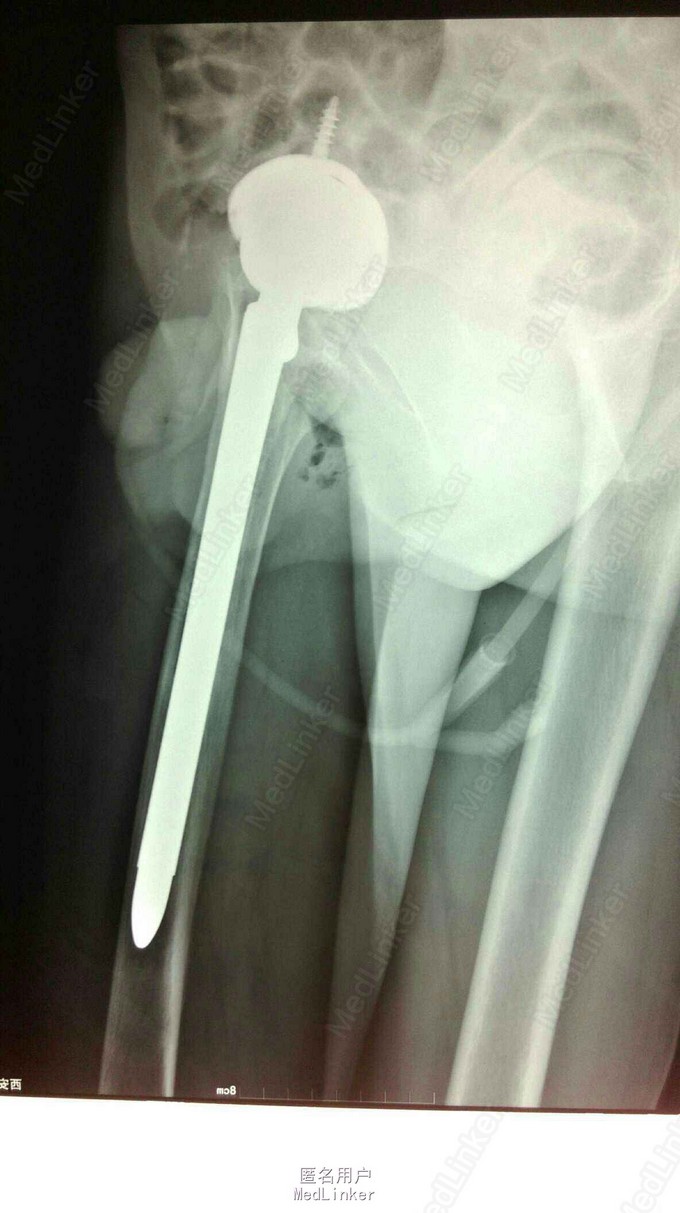

髋关节置换术后15年,疼痛2年。 15年前左股骨头坏死,在外院行股骨头置换术,2年前左下肢短缩,左髋关节疼痛,活动受限。

左下肢短缩4cm,左髋关节外展受限,叩痛阳性,左下肢血运,感觉正常。

左股骨头置换术后假体松动 完善术前检测后行髋关节翻修术,术中髋臼侧打压植骨,术后左下肢短缩1cm ,顺利出院。